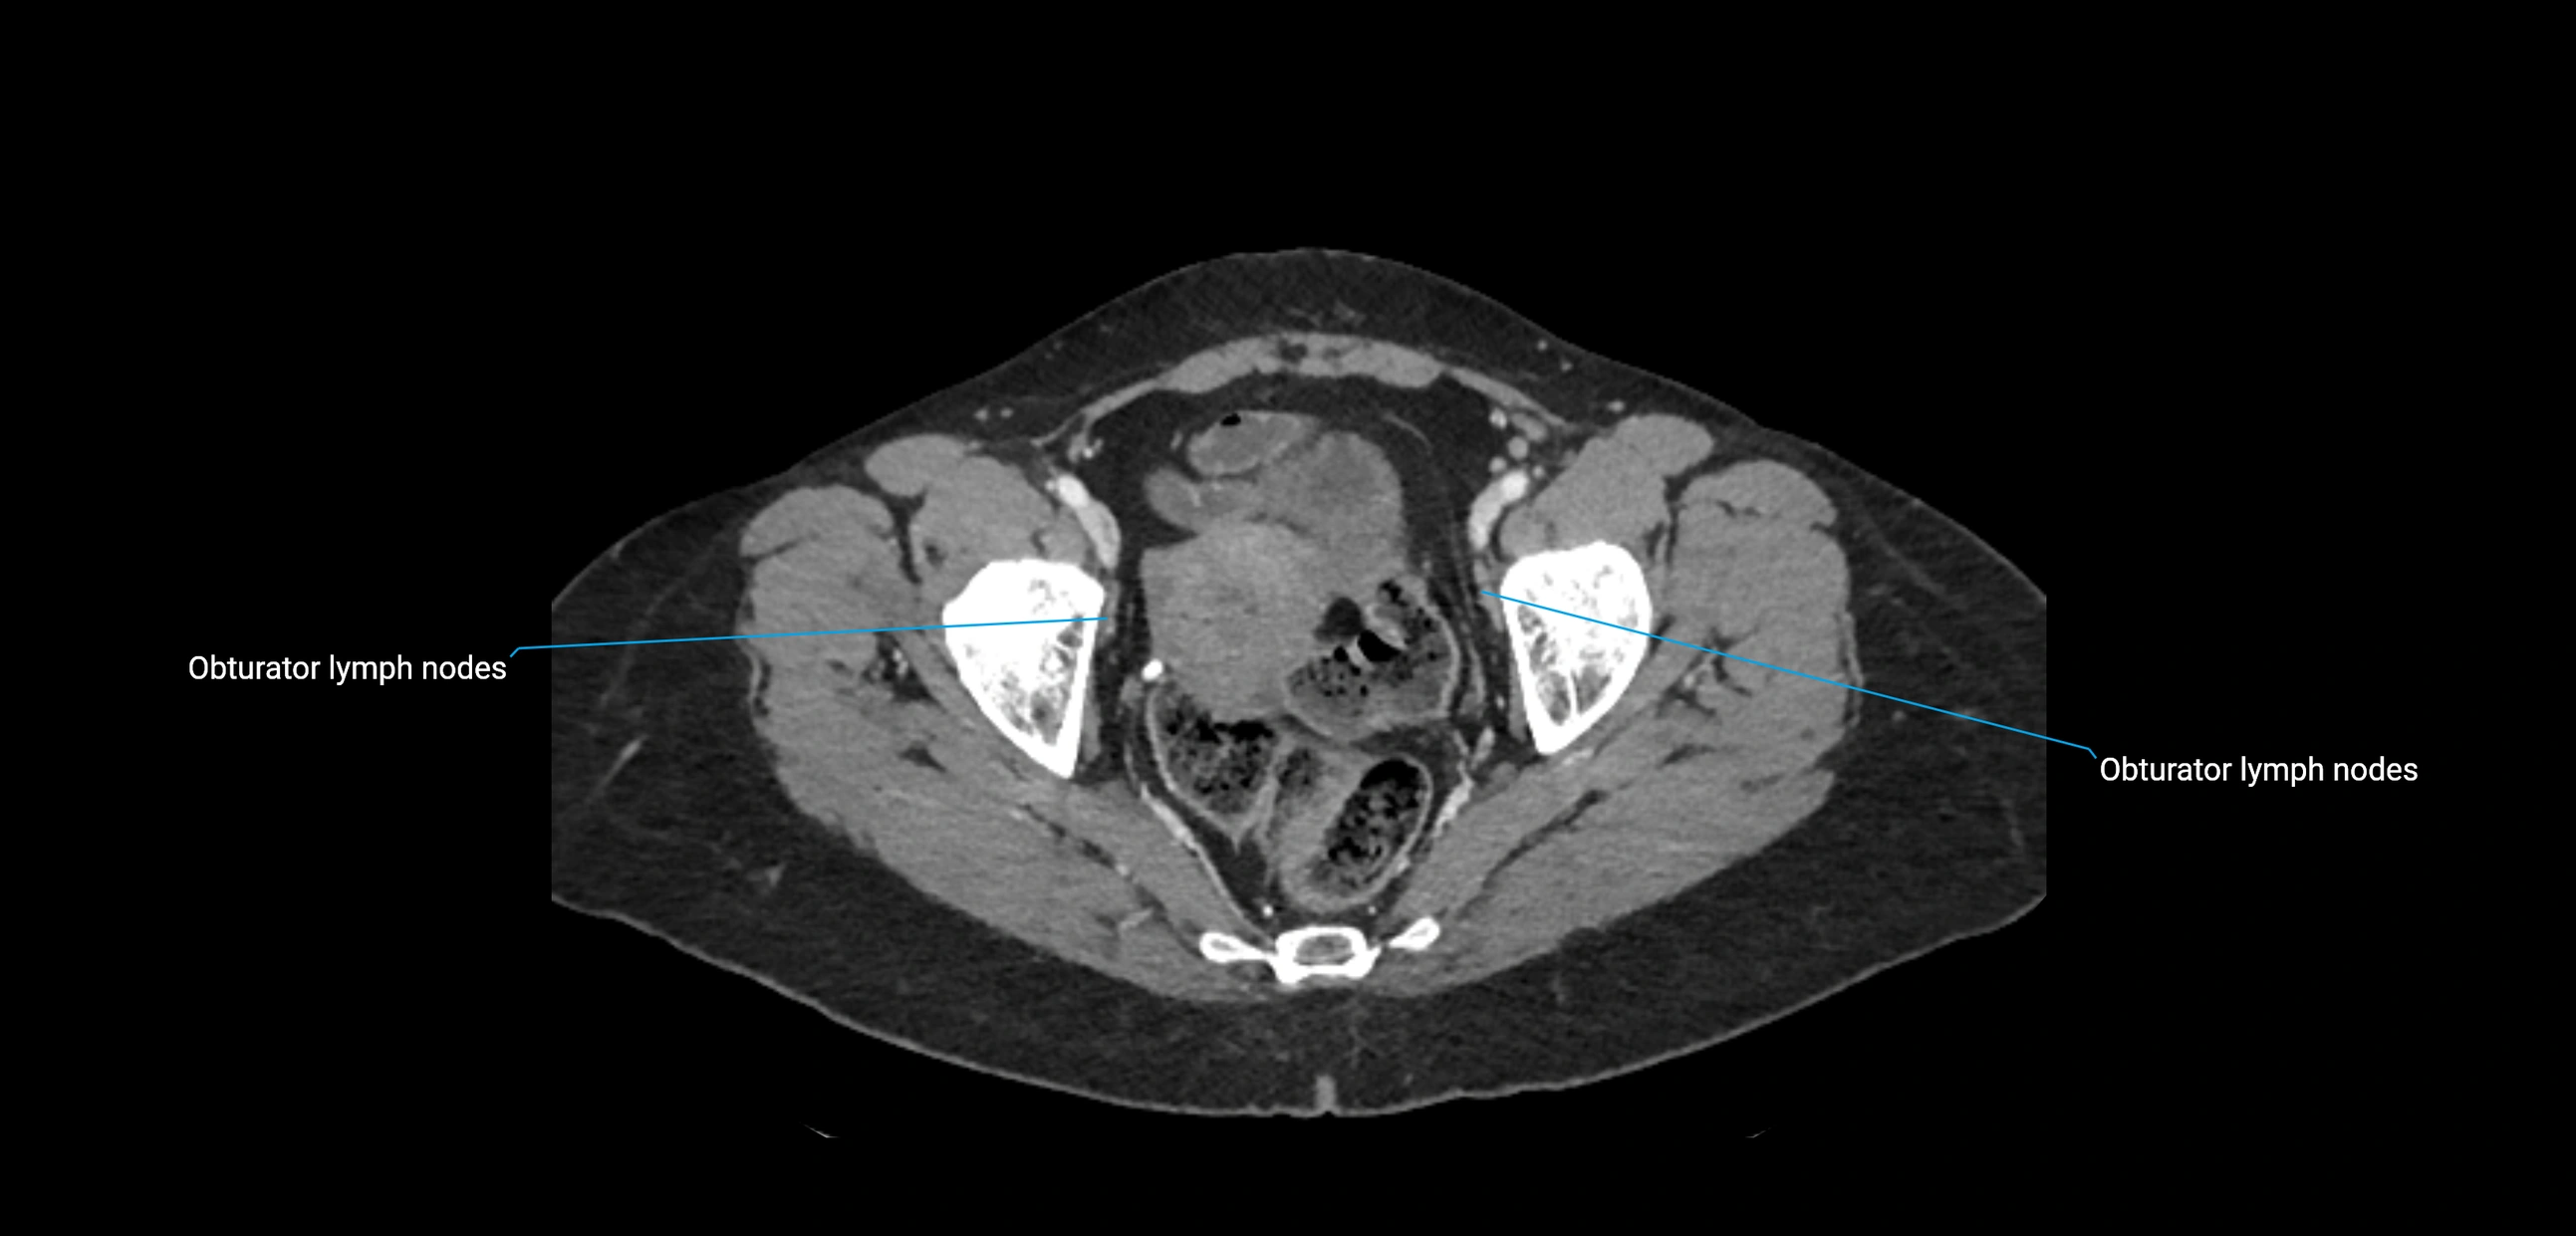

CT image

image